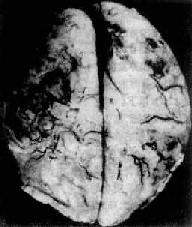

脑脓肿的发展规律和形态与全身其它器官的脓肿相似。急性脓肿发展迅速,境界不清,无包膜形成,可向四周扩大,甚至破入蛛网膜下腔或脑室,引起脑室积脓,可迅速致死。慢性脓肿边缘毛细血管和纤维母细胞(源于血管壁)增生明显,并伴有淋巴细胞和巨噬细胞浸润,形成炎性肉芽组织和纤维包膜,境界清楚。脓肿周围脑组织水肿明显,并伴有星形胶质细胞增生(图16-12)。

慢性脑脓肿

图16-12 慢性脑脓肿

右侧颞叶的脑脓肿与侧脑室相通